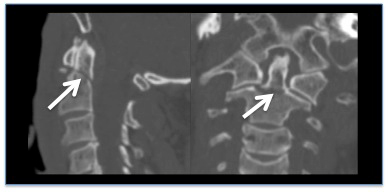

Fraturas de C2: fraturas do carrasco (espondilolistese de C2), fraturas do odontoide, fraturas laterais do corpo.[Figure caption and citation for the preceding image starts]: Reconstrução em tomografia computadorizada (TC), demonstrando uma fratura do odontoide sem desvioDo acervo pessoal de Michael G. Fehlings [Citation ends].